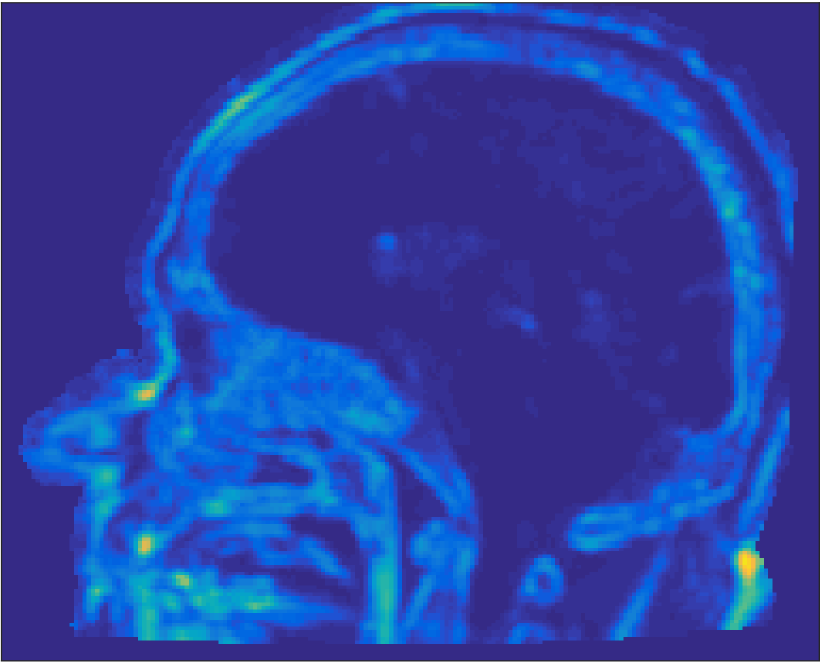

All MR images were acquired with a 1.5 T Siemens Espree scanner. The UTE images were reconstructed to 192×192×192192192192192\times 192\times 192 voxel bitmapped images with an isotropic resolution and a voxel size of 1.33 mm. The UTE sequences sampled the k-space radially with 30 000 radial spokes. CT images were acquired with a tube voltage of between 120 kV and 130 kV on either a GE Lightspeed Plus, Siemens Emotion 6 or GE Discovery 690. The in-plane pixel size varied between 0.48 mm to 1.36 mm and the slice thickness between 2.5 mm and 3.75 mm. Images of the same patient were co-registered and resampled to achieve voxel-wise correspondence between all five modes. A binary mask excluding most of the air surrounding the head was computed from the images and used to remove unnecessary data. Furthermore, to reduce the execution time of the parameter estimation phase, only 11 slices in the middle of the head of each patient was used during the parameter estimation phase, but all slices were used during the prediction phase (s-CT generation). Additional details concerning the data can be found in Johansson et al. [16]. Data from one slice of a patient is shown in Figure 3.

Refer to caption

(a) Binary mask

(b) CT

(c) First echo, 10superscript1010^{\circ}

(d) Second echo, 10superscript1010^{\circ}

(e) First echo, 30superscript3030^{\circ}

(f) Second echo, 30superscript3030^{\circ}

Figure 3: Binary data mask (panel a), CT image (panel b), The four MRI UTE sequences (panels c-f).